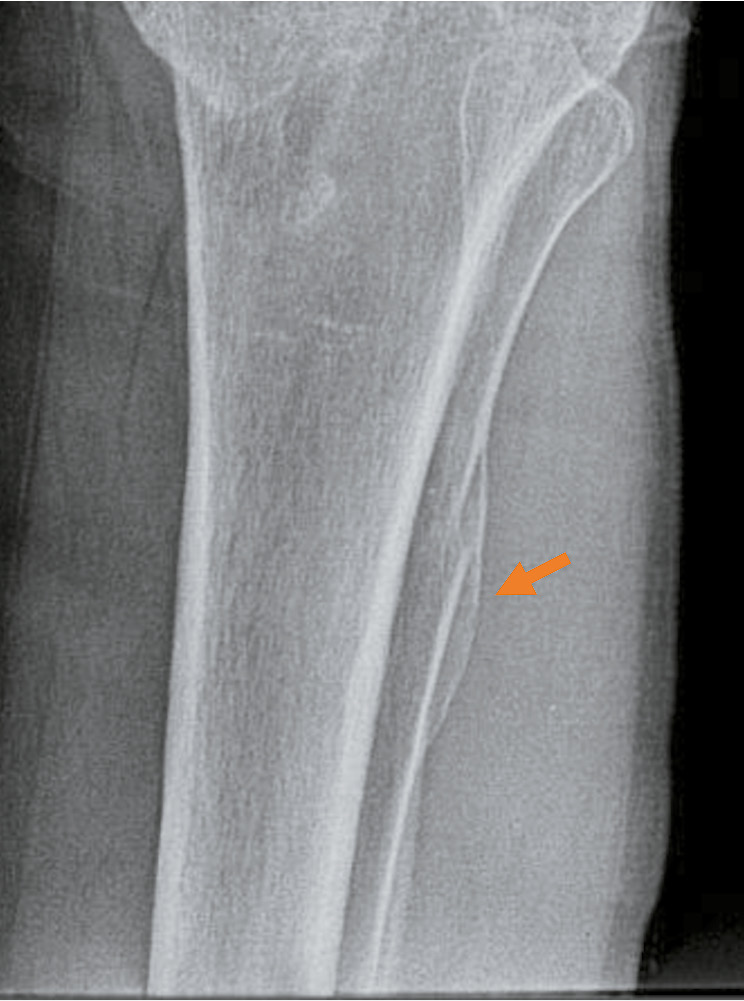

9) 271–365 суток (9–12 месяца): происходит дальнейшее постепенное закрытие линии перелома: у 17% мужчин магистральная трещина просматривается на 1/2, у 83% ― менее чем на 1/2 своей протяжённости, у женщин ― соответственно у 14% и 86%; костная мозоль плотная, по интенсивности соответствует кортикальному слою кости, равномерной интенсивности, с чёткими границами, у 23% мужчин и 19% женщин с признаками перестройки костной ткани, которые более выражены после 11 месяцев; края переломов и концы отломков не просматриваются (см. табл. 3, 5; рис. 2, 3);

Рис. 2. Перелом диафиза бедренной кости давностью 9 месяцев в условиях металлоостеосинтеза (стрелка): линия перелома нечётко просматривается на 1/2–1/3, костная мозоль равномерной интенсивности с чёткими ровными границами.

Fig. 2. Fracture of the femoral diaphysis, 9 months old, in the conditions of metal osteosynthesis (arrow): the fracture line is not clearly visible at 1/2–1/3, the callus is of uniform intensity, with clear, even boundaries.

Рис. 3. Перелом диафиза локтевой кости давностью 11,5 месяца (стрелка): линия перелома практически не просматривается, края переломов и концы отломков не визуализируются, костная мозоль с начальными признаками перестройки.

Fig. 3. Fracture of the diaphysis of the ulna, 11.5 months old (arrow): the fracture line is practically not visible, the edges of fractures and the ends of fragments are not visualized, the bone callus shows initial signs of restructuring.